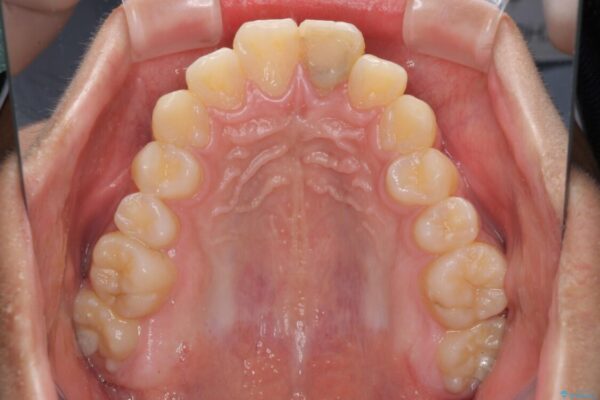

口元の突出感を気にして来院された患者様です。

上下前歯が著しく前突している状態であったので、上下左右の第1小臼歯4本を抜歯し、ワイヤー装置にて矯正治療を行うこととしました。

舌の突出癖により、前突になったと考えられたため、舌のトレーニングをしっかりと行うよう指導しました。

小学生の頃に上顎前歯をぶつけ、歯の一部が破損している状態であったので、歯根が歯槽骨と癒着して移動しない可能性がありましたが、無事に治療を終えることができました。

受験勉強と重なり、舌のトレーニングが十分に行えず、高校生としてはやや長期間の治療となりました。